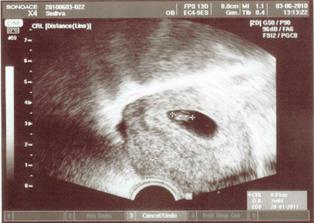

3.6.2010 opět slavíme čtvrté výročí svatby a poprvé navštěvujeme poradnu, miminko je přesně 7+0, srdíčko tluče, dostáváme pochvalu a těhotenskou průkazku